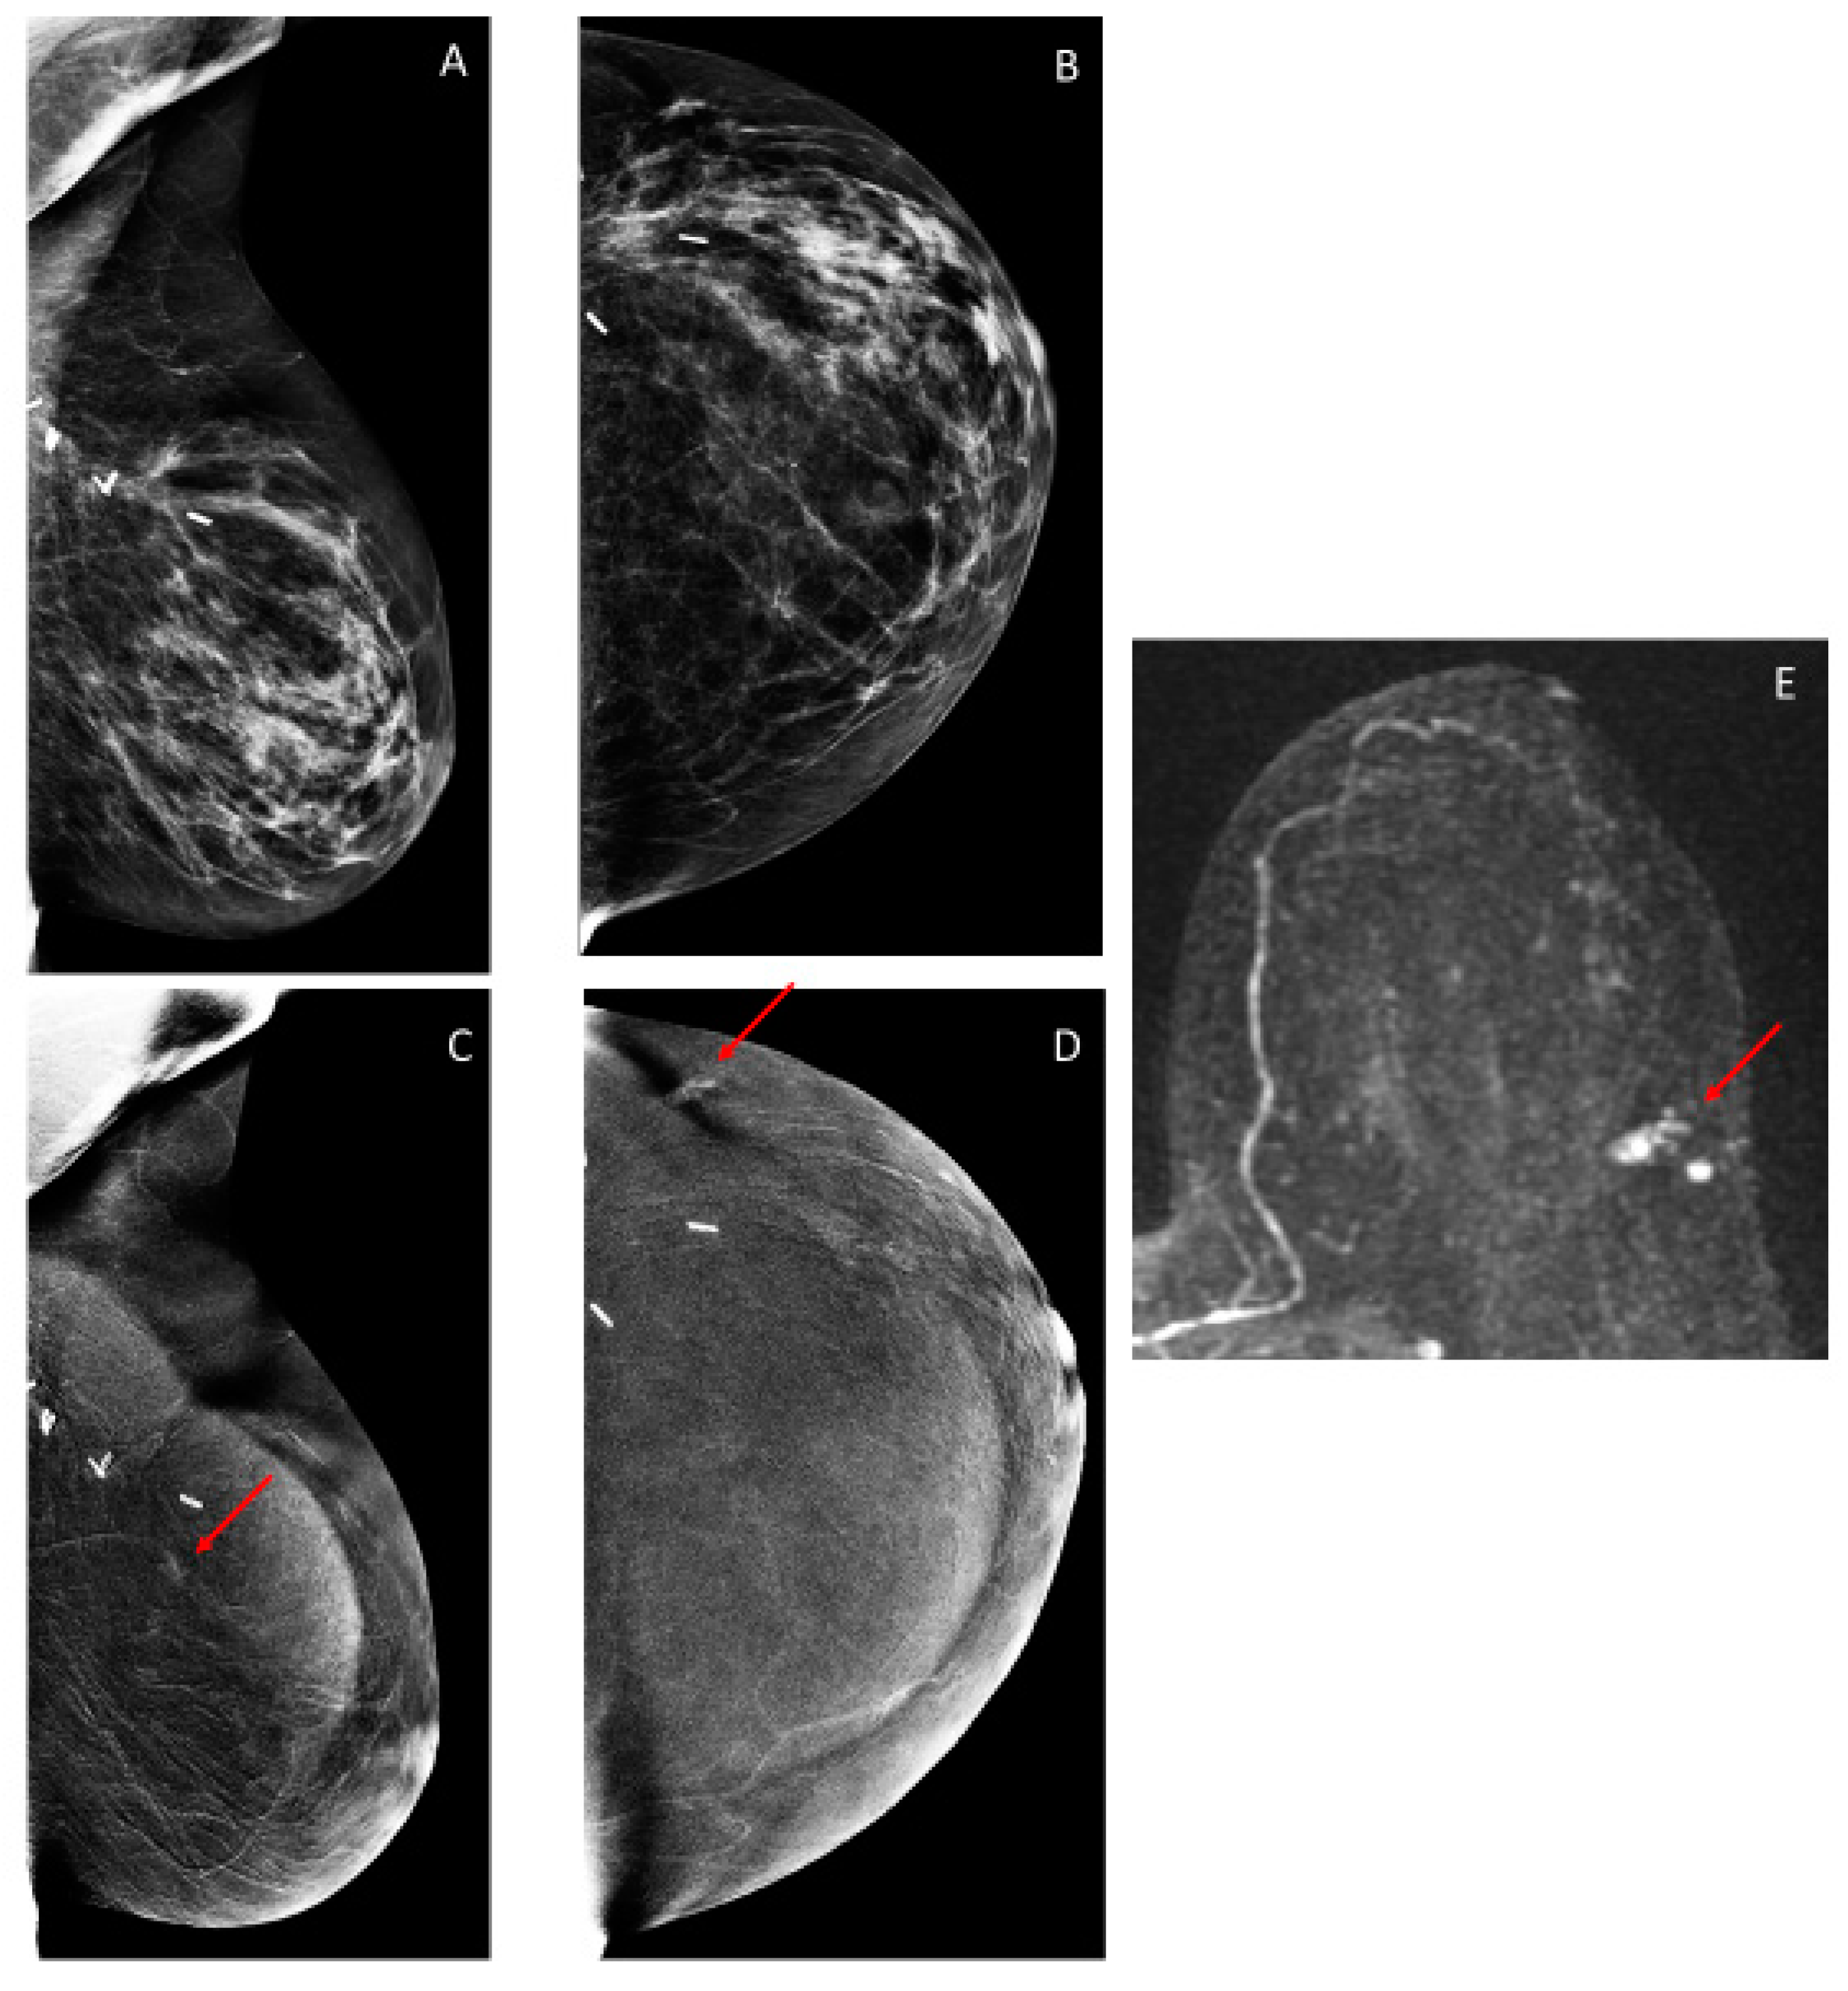

3.2. Findings on Low-Energy Images, With or Without Enhancement

3.3. Additional Findings on Iodine Images

3.4. Overall CEM Results